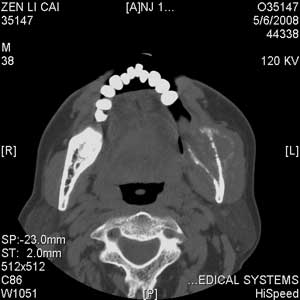

以下是引用jiangjing在2008-5-28 15:56:00的发言:[br]下颌骨左侧部骨质破坏,轻度膨胀,瘤骨形成,软组织肿胀考虑 恶性骨肿瘤-----肉瘤类